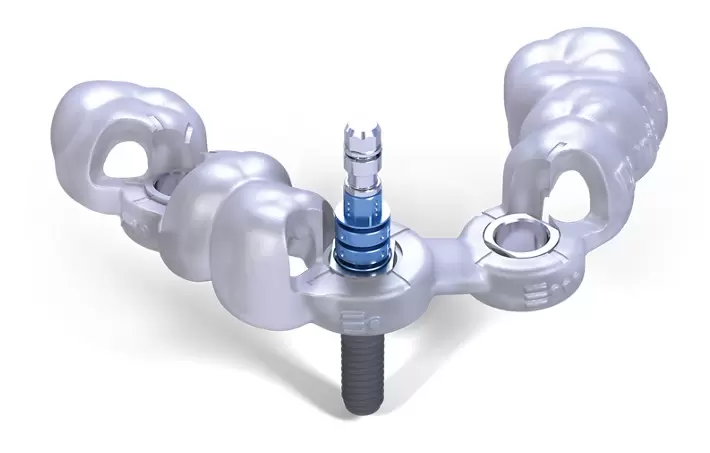

Chân răng của chúng ta, được tiến hóa vị trí dựa trên tác động của lực nhai hàng ngày. Mỗi chân răng đều có hướng trùng khít với hướng truyền lực nhai. Vị trí trụ dọc của chân răng nằm trùng với điểm tác động lực tối đa theo chiều đứng. Chân răng implant được gọi là đặt chính xác khi vị trí. Hướng của nó trùng khít với vị trí tác động lực và phương truyền lực.

Một chân răng đặt đúng vị trí sẽ giúp lực nhai truyền vào đúng trục. Từ đó giúp răng implant ăn nhai tốt hơn, ít bị tiêu xương hơn và sẽ bền vững hơn.

Mặt khác, trong Quy Trình Trồng Răng Implant, giải pháp trồng răng implant cá nhân hóa. Chân implant cần đặt chính xác độ sâu. Để phần trong lợi của trụ phục hình cá nhân hóa có không gian. Từ đó tái thiết lại mô nha chu và tái lập khoảng sinh học quanh răng implant. Khi implant đặt quá nông, Customized Abutment sẽ không thể thiết lập được hàng rào sinh học. Khiến cho răng implant dễ bị tổn thương hơn từ những tác nhân trong khoang miệng.